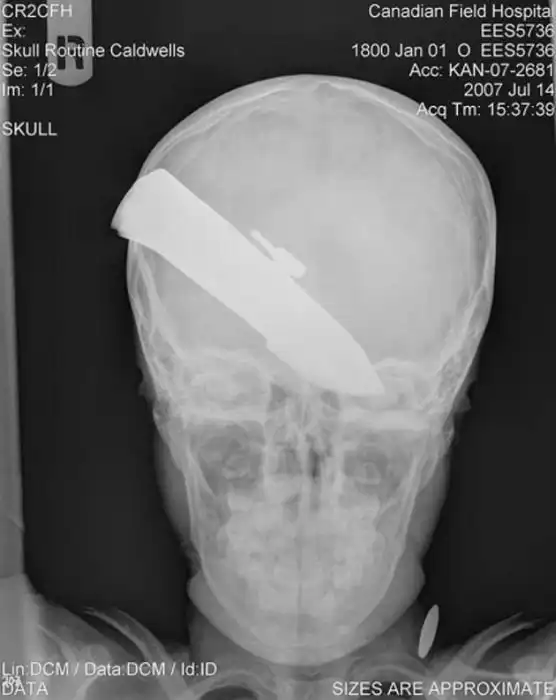

Жуткие рентгеновские снимки

Порой даже не верится, с какими странными и необычными повреждениями в травматологию могут поступить пострадавшие. Всю эпичность профессии врачей травматологии могут с легкостью подтвердить рентгеновские снимки.